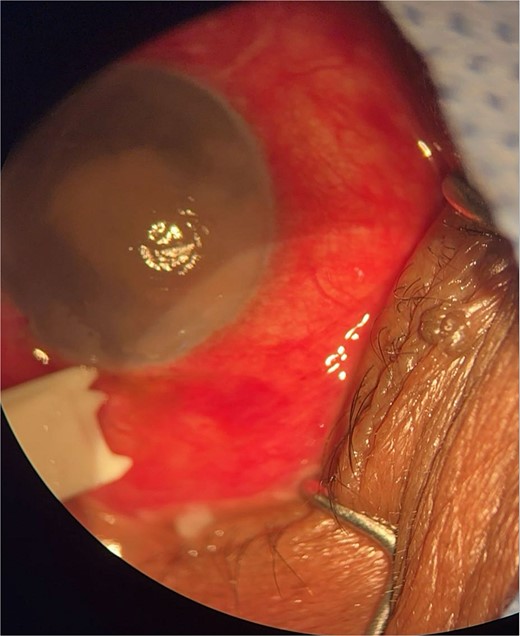

Patient 3: A 63-year-old Saudi female reported pain and decreased vision in her right eye. On examination 4 days post-surgery, her vision was PL. Examination findings included severe conjunctival injection (Fig. 5). B-scan (Fig. 6). Treatment included vitreous tap and intravitreal antibiotics.

Surgical microscope examination showing hypopyon, chemosis, ciliary, and conjunctival injection in patient 3.